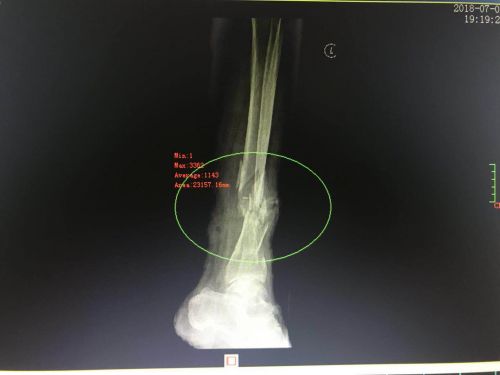

影像资料显示,左侧胫腓骨开放性、粉碎性骨折并错位。

检查发现,老人身上有多处皮肤软组织损伤,左侧胫腓骨开放性、粉碎性骨折,伤情非常严重。创伤骨病科魏磊平主任医师、徐勇强主治医师等立即为老人做了简单的伤口处理,然后送入手术室。

4日凌晨,经过近2个小时的紧张操作,老人成功接受“左侧胫腓骨骨折复位外固定架+负压引流”手术。魏磊平主任医师表示,由于皮肤有缺损,老人还需接受植皮手术,伤口感染的风险也很大,需密切观察病情变化。